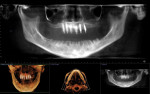

Placement of the six implants was planned using a 3D model created from the CT scan data (Figure 4 and Figure 5). Because of the sinus pneumatization, it was necessary for all six implants to be located in the anterior, rather than spread more evenly throughout the arch. A surgical guide (3DDX Surgical Guide, 3D Diagnostix, www.3ddx.com) for coDiagnostiX™ (Dental Wings GmbH, www.codiagnostix.com) was designed and fabricated to facilitate the flapless placement. On the day of surgery, this was secured using fixation pins (Figure 6).

Immediately after implant placement, a panoramic radiograph was taken (Figure 11). It confirmed that none of the implants were impinging on the sinus cavity. A postsurgical CT scan (Figure 12) confirmed that placement of the 20-degree angled implants followed the natural slope of the maxillary ridge, creating adequate prosthetic space.